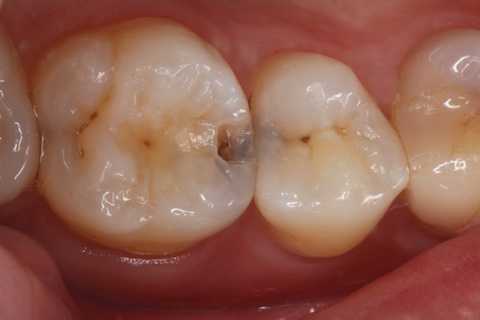

20代女性、右上6、咬合性外傷による隣接面カリエス

クラックが気になるのだが、象牙質には広がっていないようだったので、このまま充填した。

では時系列でどうぞ